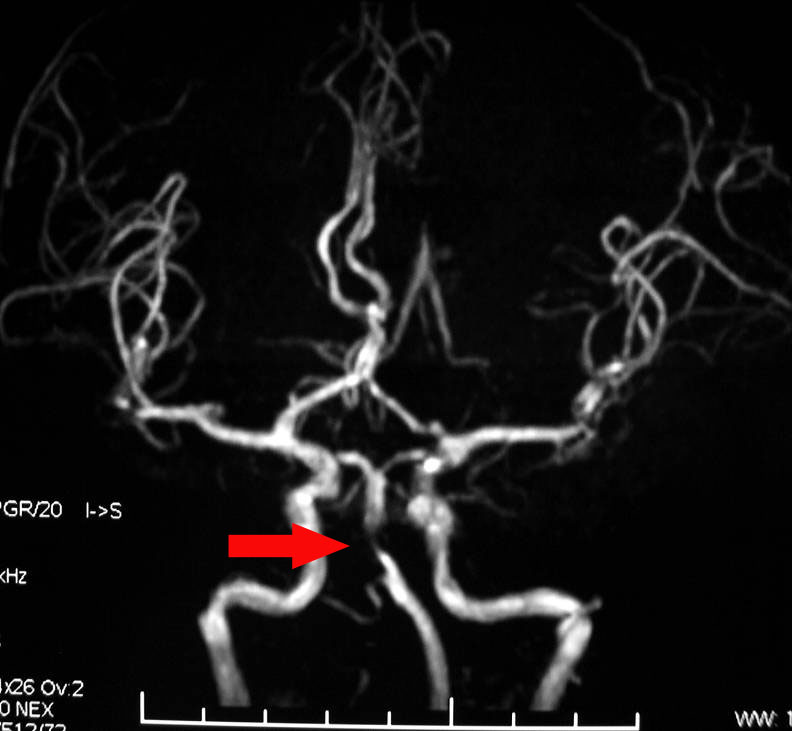

脑动脉狭窄是造成缺血性脑血管病的一个重要病因和危险因素。脑动脉狭窄使得经过脑血管的血液减少,脑细胞就会缺血死亡。了解脑动脉狭窄的症状分型对及时治疗有很重要的作用。

脑动脉狭窄症状分型

非症状性狭窄

症状性狭窄(ICA、CA狭窄>70%,MCA、BA狭窄>50%)

Ⅰ型狭窄:狭窄血管供血区域缺血,出现相关区域缺血的临床表现。

Ⅱ型狭窄:狭窄引起的侧支血管供血区域缺血(盗血),狭窄血管供血区得到代偿,出现盗血综合症。

Ⅲ型狭窄:混合型